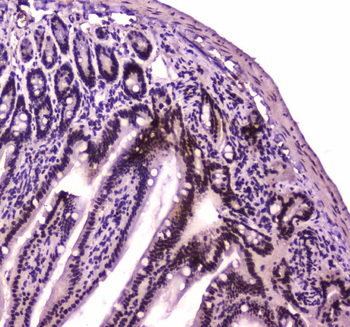

Immunohistochemistry of paraffin-embedded human colon using orb631314 (SMARCA4 Antibody) at dilution of 1:50.